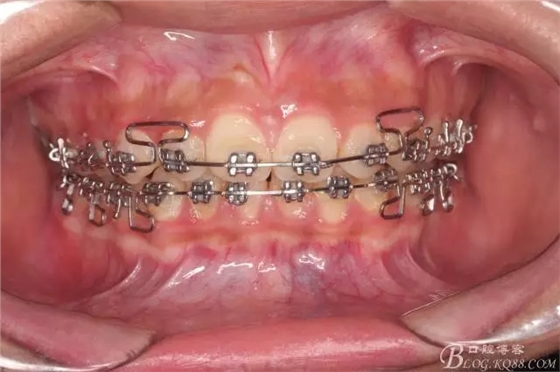

看看口內照吧!真象“大暴牙”v假象“大暴牙”

三度深覆合,三度深覆蓋,尖牙,磨牙均二類關系!